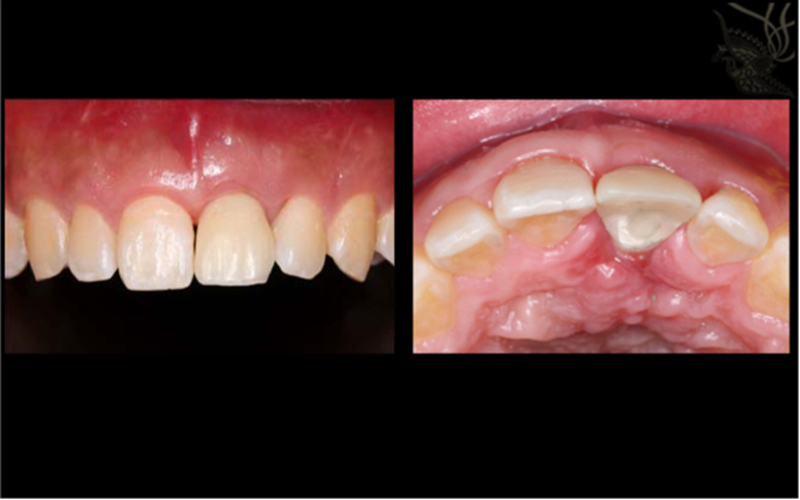

1.使用螺絲固位修復方案 2.軟組織恢復效果佳,達到美學效果

術(shù)后照片